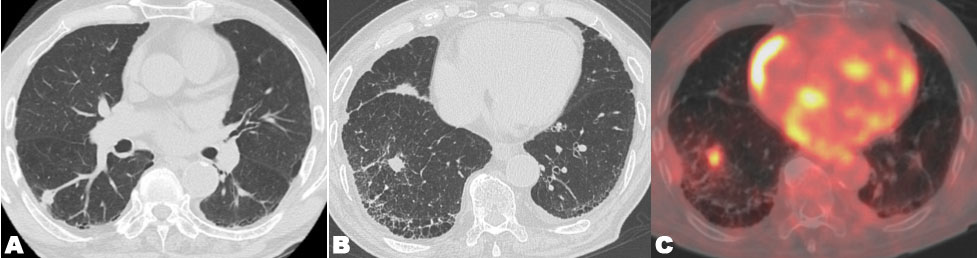

An 89-year-old man was diagnosed with stage I (T1cN0M0) adenocarcinoma in right lower lobe (Figure 4A). He had no previous history of smoking and an unremarkable medical history. He received initial SBRT at an irradiation dose of 48 Gy in 4 fractions at the isocenter (Figure 5A). The maximal PTV dose was 48 Gy. The MLD was 3.6 Gy, lung V5 was 23%, and lung V20 was 3.0%. Follow-up examinations were conducted 1, 3, 6, 9, and 12 months after initial SBRT in the first year, and then every three months. Although the lung tumor shrank, three years and six months after initial SBRT, a new lesion, distant form the lung tumor, has developed in the same lobe (right lower lobe). Serial enlargement and increased uptake on FDG-PET/CT were evident (Figure 4B and Figure 4C), which led to a diagnosis of lung metastasis or new primary lung cancer without pathological proof and, thus, the patient received repeat SBRT. The repeat SBRT irradiation dose was 50 Gy in 4 fractions (Figure 5B). The maximal PTV dose was 50 Gy. The MLD was 3.1 Gy, lung V5 was 18%, and lung V20 was 4.0%.

Figure 4: (A) Chest CT showed a solid nodule in the right lower lobe. (B) Chest CT showed a newly developed solid nodule in the right lower lobe. (C) 18-FDG PET/CT showed a high uptake for a newly developed solid nodule.